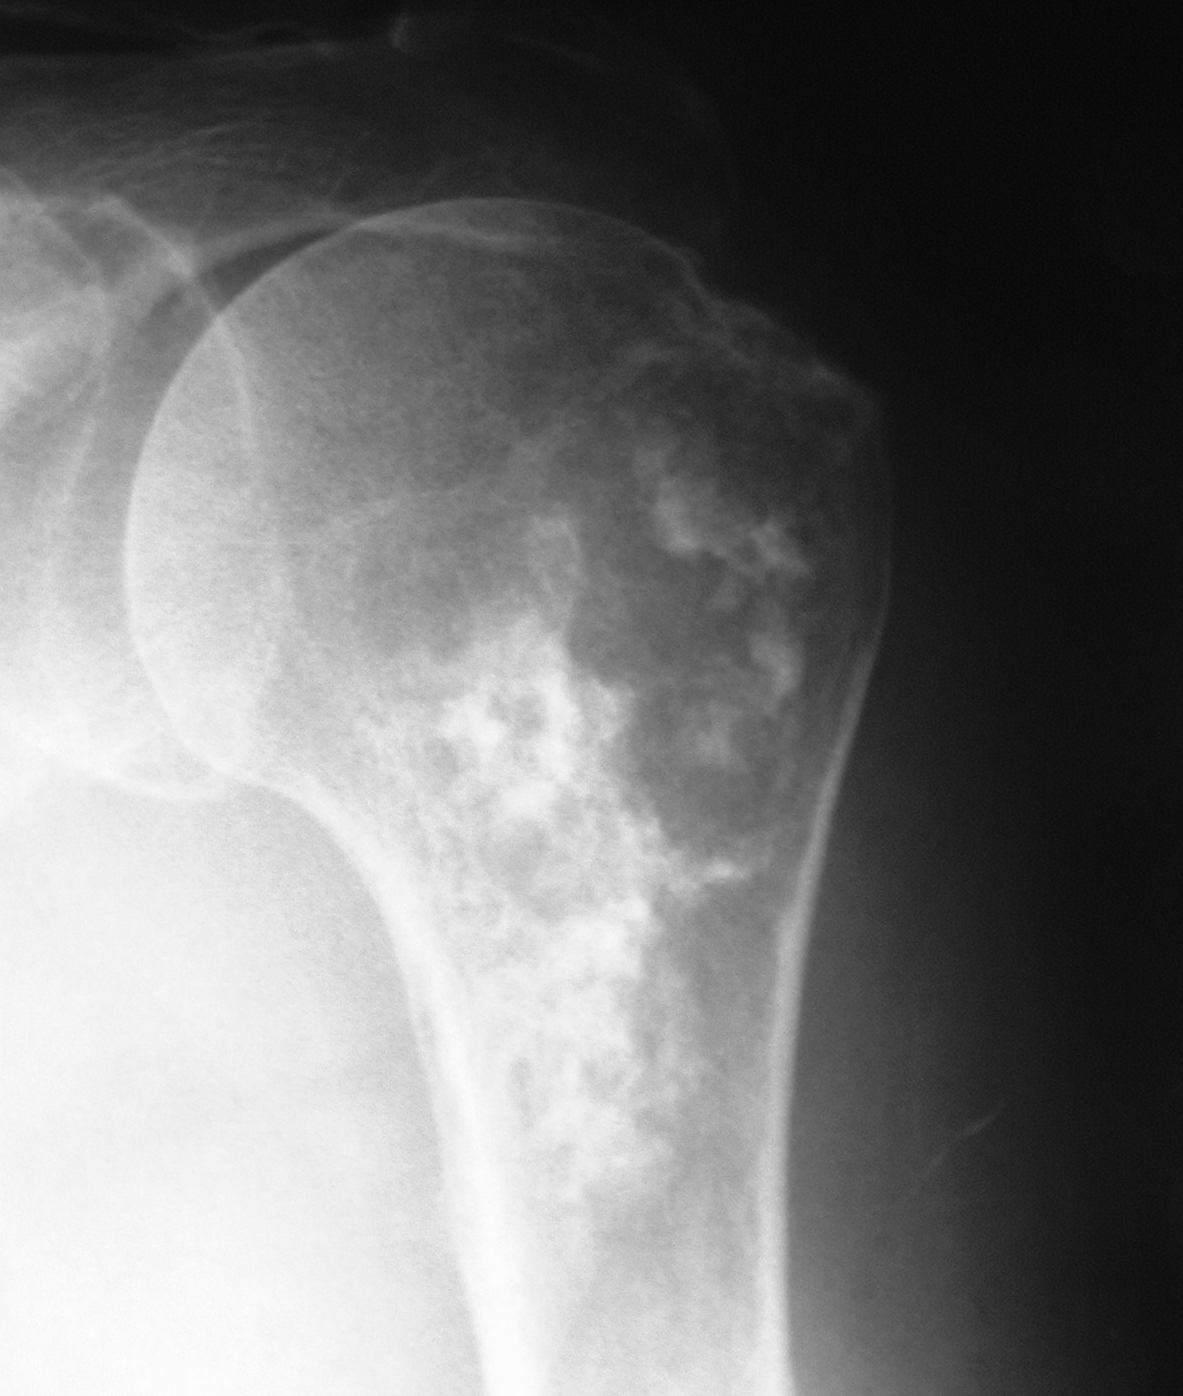

Рентгеновские снимки саркомы плечевого сустава